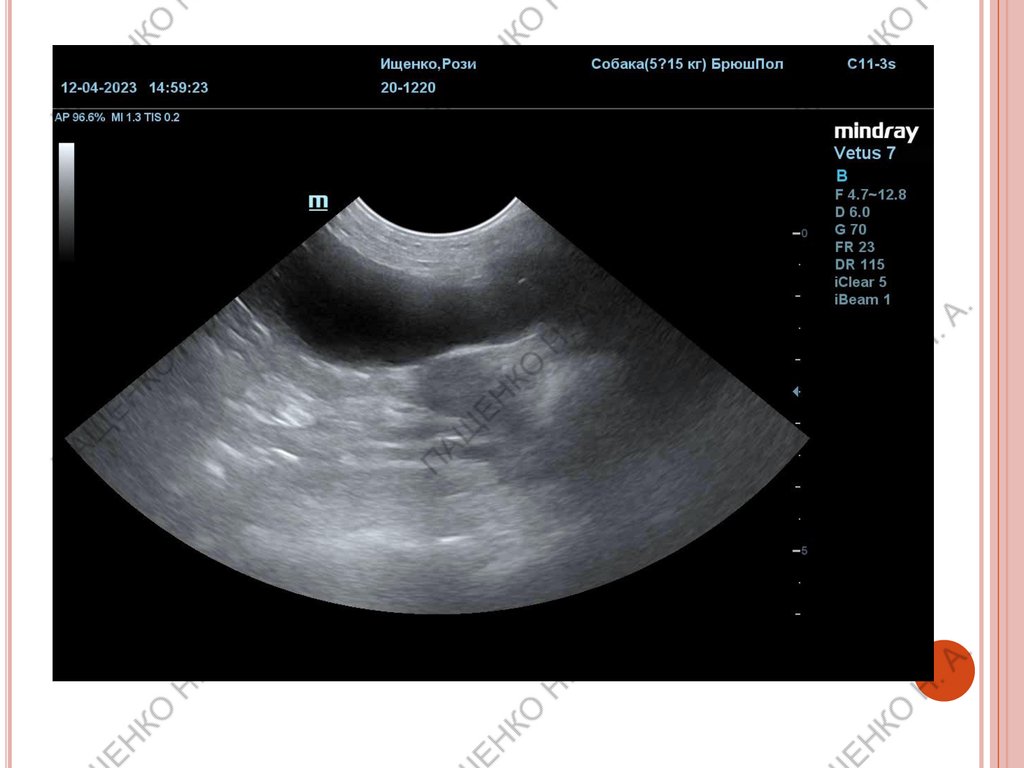

РАННИЙ СРОК (ПРИМЕРНО 22-25 ДНЕЙ)